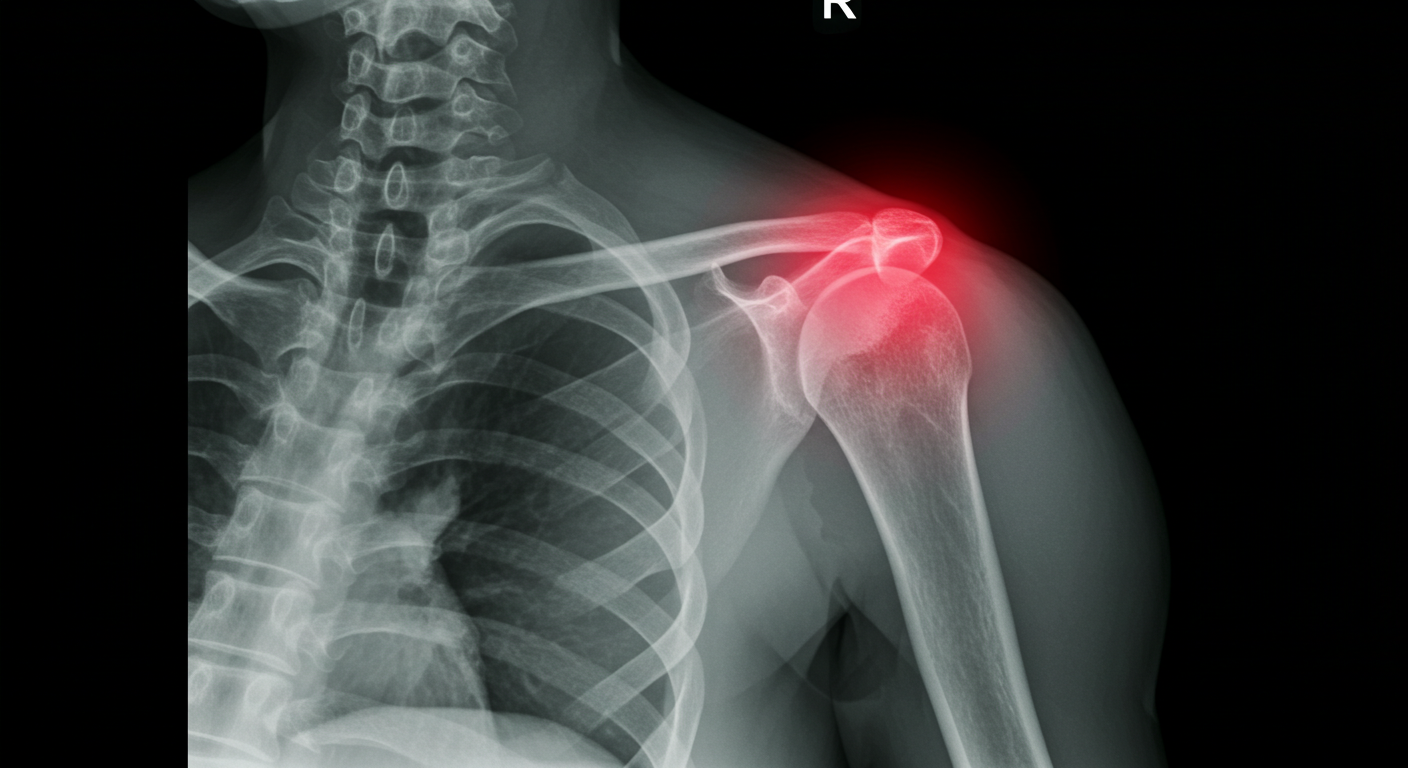

가장 흔한 탈골, 어깨 탈구!

관절 중에서도 어깨 관절은 특히 탈골이 잘 되는 부위로 유명함. 왜냐고? 어깨 관절은 팔 뼈(상완골)와 어깨뼈(견갑골)가 만나서 이루어지는데, 다른 관절에 비해 움직임 범위가 엄청 넓거든. 360도 회전도 가능할 정도니까. 그래서 그만큼 안정성이 떨어질 수밖에 없음. 어깨 관절은 마치 골프공이 티 위에 얹혀 있는 것처럼 불안정한 구조라, 작은 충격에도 '툭' 하고 빠지기 쉬운 거지.